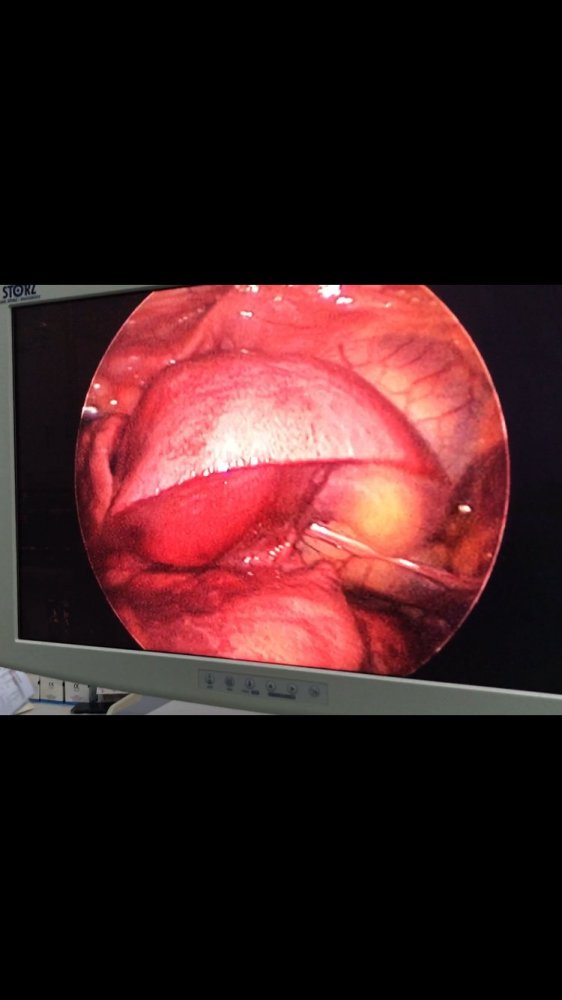

MediastinalTeratoma .Torokoskopik teratomanın eksiziyası

Daha bir çətin əməliyyat 8 yaşlı pasientdə döş boşluğunda törəmə- Ağciyərin orta payı üzərində böyük həcmli törəmə Teratoma. Torokoskopik törəmənin eksiziyası

Dr. Toğrul Ömərov